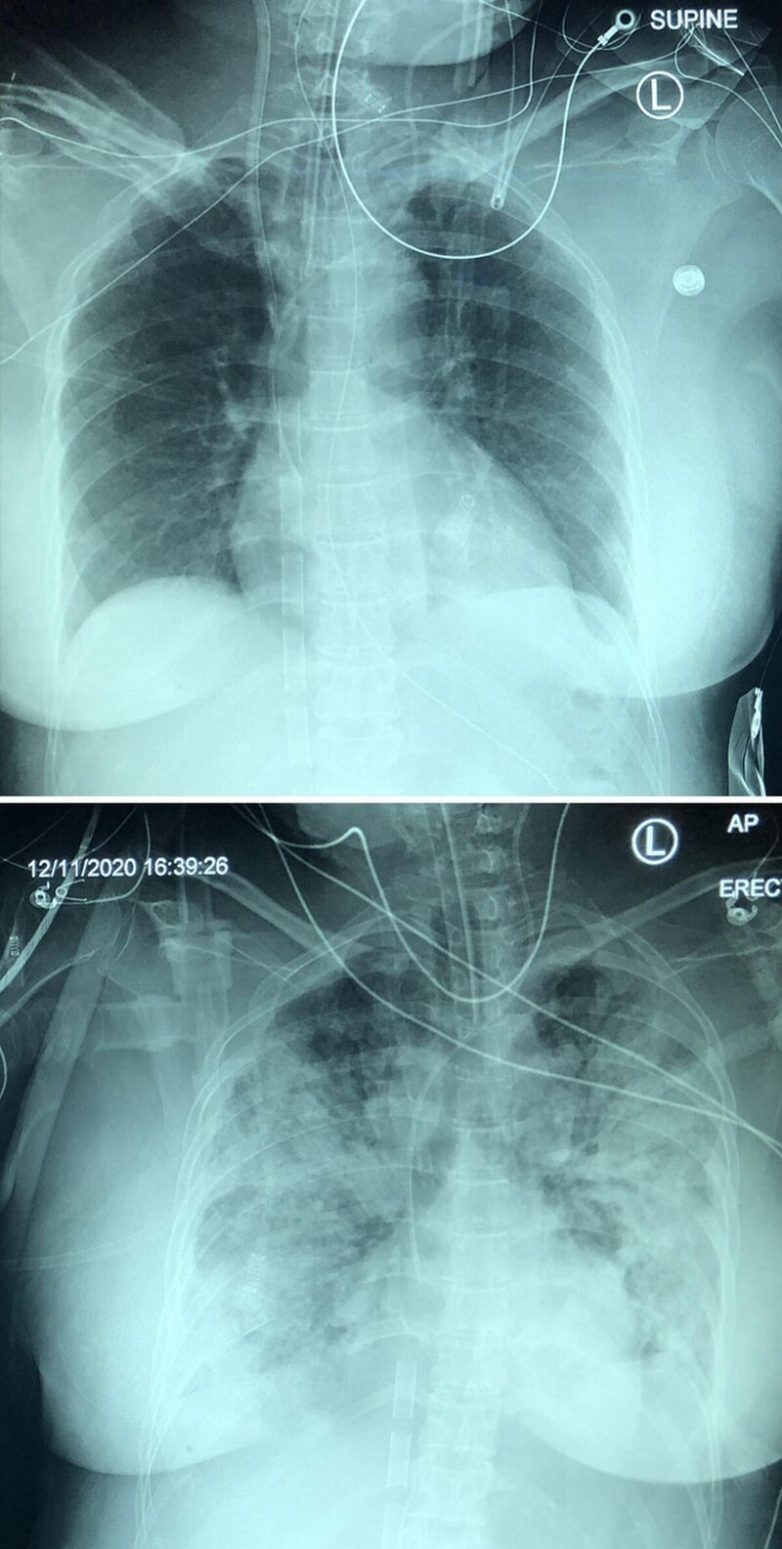

Развитие ковидной пневмонии в течение 5 дней